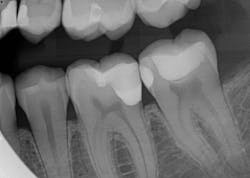

Caries lesions were removed and air abrasion was employed to remove impurities on the unprepared tooth surfaces and create increased surface area for bonding. Preparation of the class II carious lesions revealed demineralization on the adjacent tooth structure (figure 3). When lesions such as these are discovered, dentists are often at a crossroads whether to intervene or monitor the area for progression. It is my experience that these early caries lesions can be predictably arrested with resin infiltration (figure 4), and that no intervention usually results in the progression of caries.

In this case, lateral access was achieved by the preparation of the adjacent teeth as part of the proposed treatment plan. Early caries lesions that are noted on radiographs that are not accessible in cases such as this one can be accessed by placing an orthodontic spacer. This patient was restored with direct composite bonding (figure 5) and these restorations have proven to have a favorable long-term outcome (figure 6).